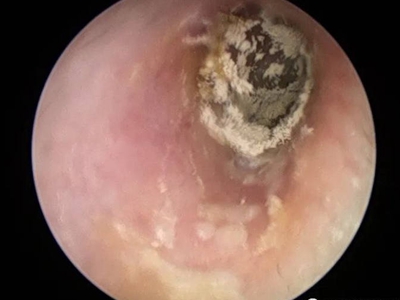

外耳道

脱屑 · 化脓

外耳道炎耳朵里有脓性分泌物图

外耳道炎患者的外耳道黏膜潮红,伴随有肿胀感,并且附着大块黄白色脓痂,形状不规则,脓痂上有白色细密鳞屑,患者自觉耳部疼痛。